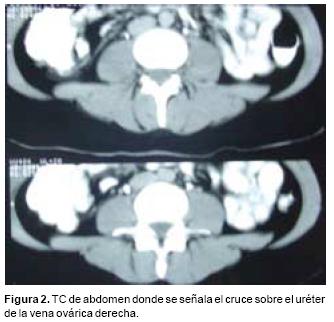

Se realiza pielografía ascendente derecha en la que el paso del medio de contraste es filiforme en un segmento de 3 cm. a nivel de L4–L5. La TC de abdomen muestra adelgazamiento del uréter en el cruce de la vena ovárica derecha, (Figura 2).

Es característica la ausencia de dilatación pieloureteral importante y el diagnóstico por estudios de gabinete conjuga la utilización de la urografía excretora acompañada de una pielografía ascendente, demostrando por TC o venografía el cruce de la vena gonadal. El tratamiento quirúrgico con resección–ligadura de la vena ovárica tiene un excelente pronóstico.